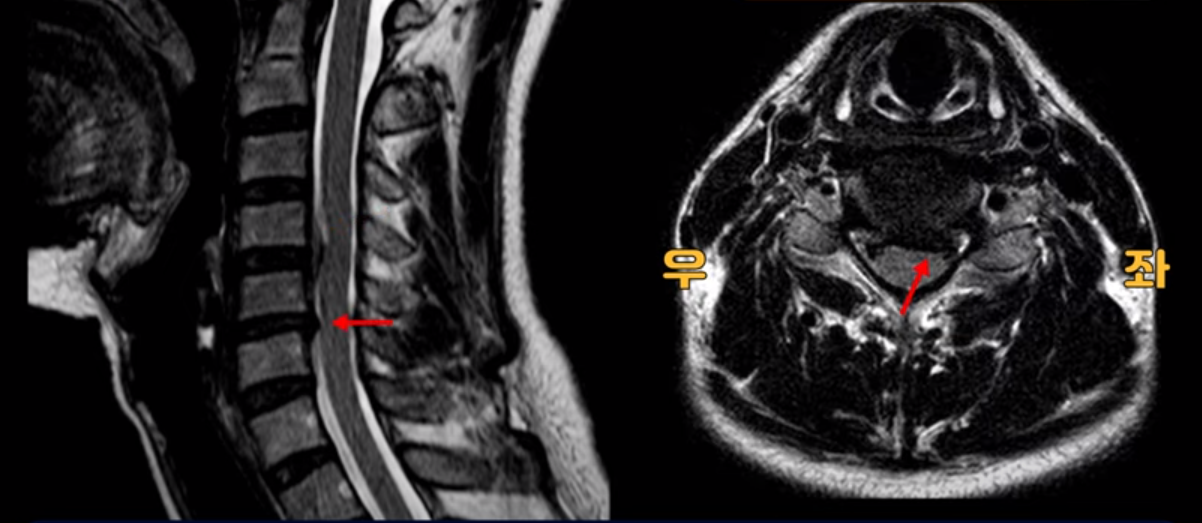

우선 이분 MRI를 보기 전에 이분 증상에 대해 말씀 드리면 오른쪽 팔저림과 방사통 및 어깨 통증이 있습니다. MRI를 보면 4번 5번에 디스크 파열이 보입니다.

밀려나온 디스크가 위로 타고 올라가 있는데 보시다시피 가운데로 밀려 나와 있습니다.

그래서 이게 오른쪽 통증의 원인일 수도 있고 아닐 수도 있습니다. 5번 6번은 왼쪽으로 밀려 나와있으니까 오른쪽 통증의 원인이 아닙니다.